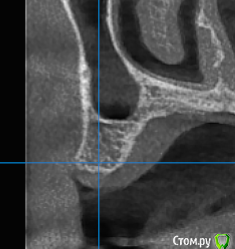

gum Опубликовано 3 декабря, 2018 Автор Поделиться Опубликовано 3 декабря, 2018 (изменено) Спасибо за своевременные советы. Сделал закрытый по месту 15 только PRF. По месту 16 с графтом Изменено 3 декабря, 2018 пользователем gum Ссылка на комментарий

Dman Опубликовано 4 декабря, 2018 Поделиться Опубликовано 4 декабря, 2018 Спасибо за своевременные советы. Сделал закрытый по месту 15 только PRF. По месту 16 с графтом Снимок.PNGпо снимку 15 просто торчит в пазуху. Это не критично? Ссылка на комментарий

gum Опубликовано 4 декабря, 2018 Автор Поделиться Опубликовано 4 декабря, 2018 Понять торчит он в пазуху или нет по данному снимку не возможно, только предположить. Ввиду того, что 15 без графта картина такая и будет на снимке. Во время операции перфорации мембраны не было, слизистая поднята за счет PRF и собственно имплантата. 1 Ссылка на комментарий

Smileee Опубликовано 4 декабря, 2018 Поделиться Опубликовано 4 декабря, 2018 Понять торчит он в пазуху или нет по данному снимку не возможно, только предположить. Ввиду того, что 15 без графта картина такая и будет на снимке. Во время операции перфорации мембраны не было, слизистая поднята за счет PRF и собственно имплантата. Можно подробнее как вы это сделали? Внесли PRF и остеотомом/кюретой протолкнули его в пазуху или как-то иначе? Ссылка на комментарий

gum Опубликовано 4 декабря, 2018 Автор Поделиться Опубликовано 4 декабря, 2018 Да, остеотомом приподнимаете слизистую и вносите. Я использовал гладилку и остеотом для внесения PRF Ссылка на комментарий